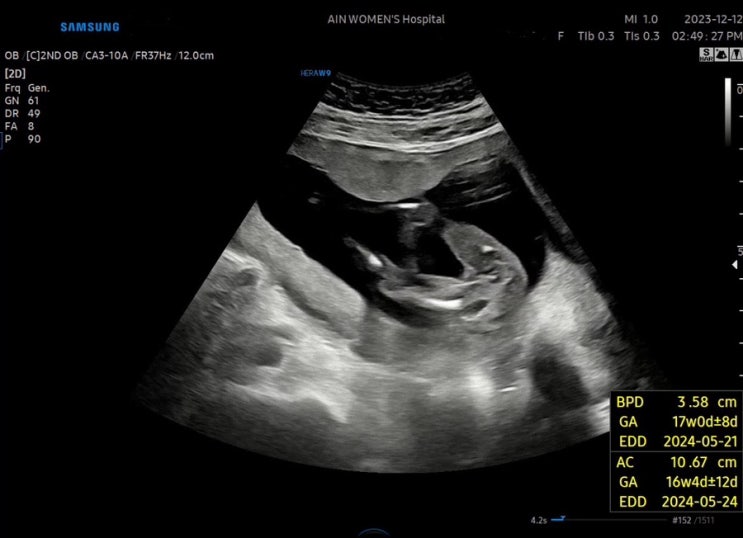

안녕, 안뇽! 20주 / 중기정밀초음파

2024. 01. 13 _ 20주 5일 16주 1일에 마지막 진료를 보고 거의 5주가 다 되어 안뇽이를 보고 왔다 . 보고싶...